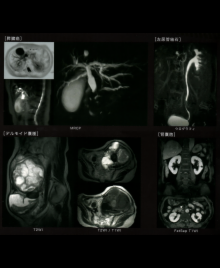

<MRI>

頭部 T1画像、T2画像

FLAIR画像

Dw画像、ADC画像

T2*画像

脂肪抑制画像

MRA画像(3D画像)

造影MRI

ミエログラフィー

体幹 T1画像、T2画像

MRCP